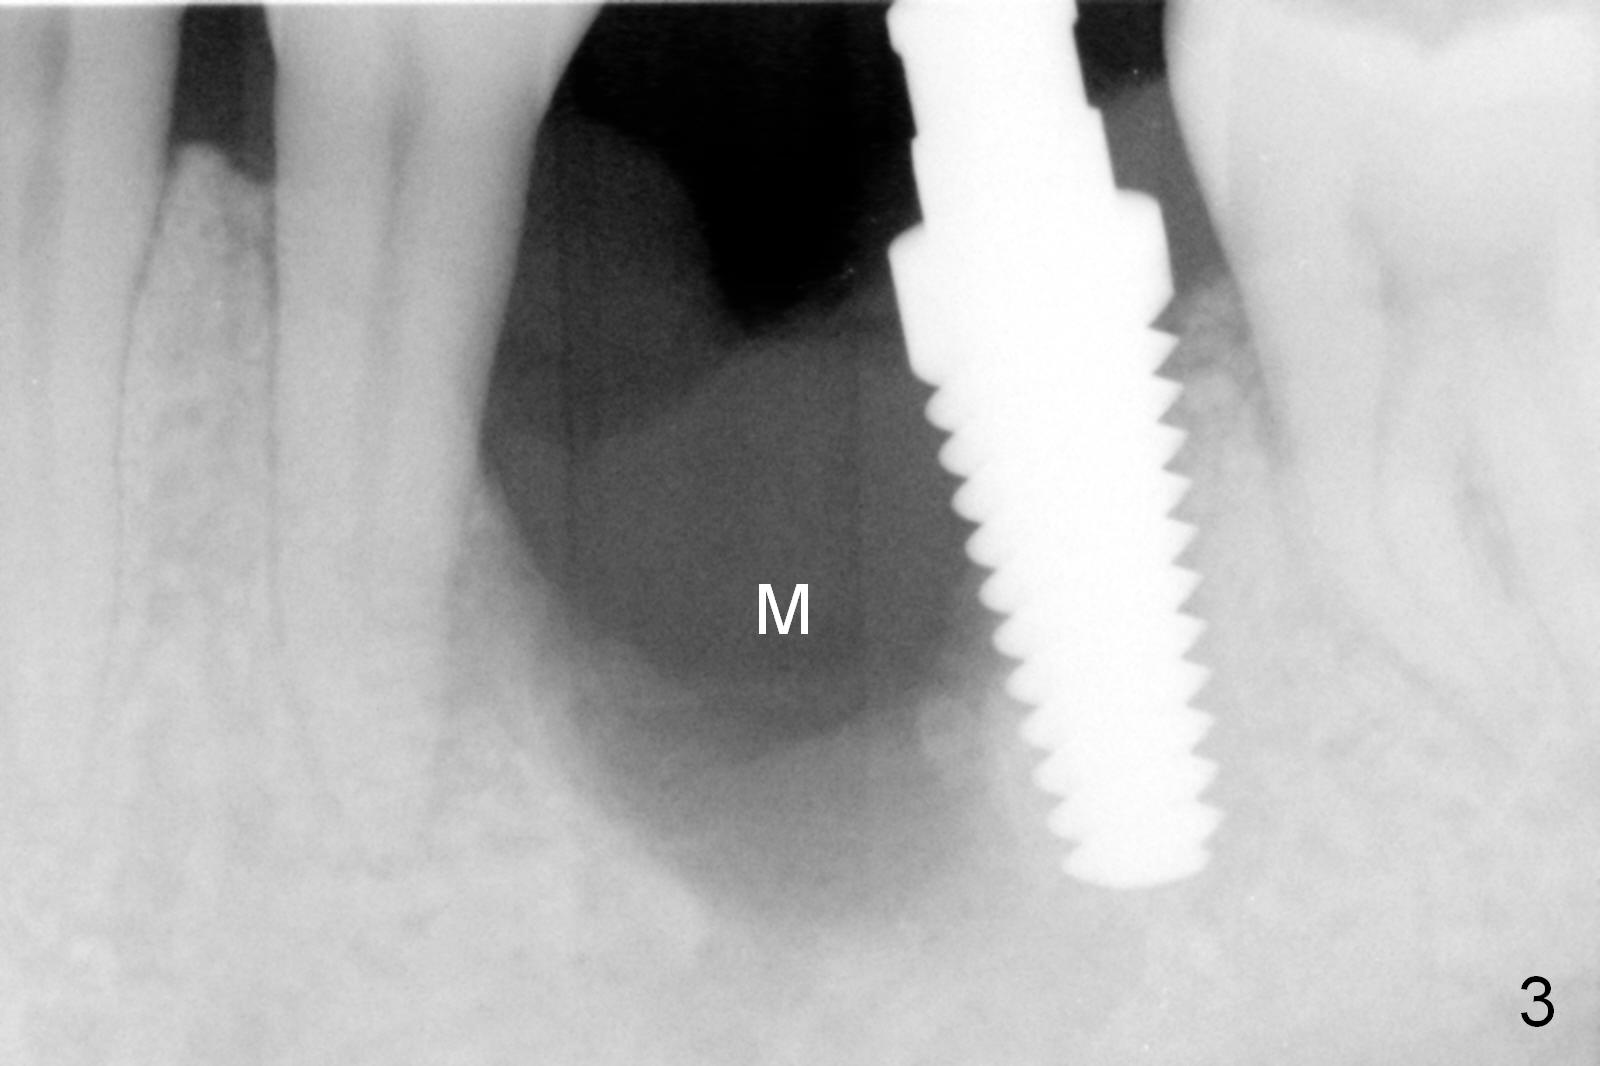

Considering the severe bone loss in the meisal socket, socket preservation is indicated if immediate implant is not feasible.  Preop exam shows that the mesiobuccal gingival recession (Fig.1 MB) is not as severe as the mesiolingual one (Fig.2 ML).  Because of oozing from the mesial socket, buccal envelop incision is made with flap raising to increase visibility.  Probably due to periodontal infection, pain control is difficult.  Osteotomy buccal to the Inferior Alveolar Canal proves to be risky.  In addition, osteotomy in the mesial socket is more difficult than the distal one (Fig.3).  Once the osteotomy depth is determined relative to the superior border of the Inferior Alveolar Canal (4 mm), the osteotomy depth increases by 2 mm.  A 5.5x10 mm implant is placed with insertion torque ~ 35 Ncm (Fig.4); a 15 ° angled abutment (5.5 mm in diameter, 4 mm in cuff) is placed mesially.  Then the abutment is turned lingually favorable for restoration (Fig.5), the remaining socket is filled with allograft/Osteogen (*) and Collagen Plug.